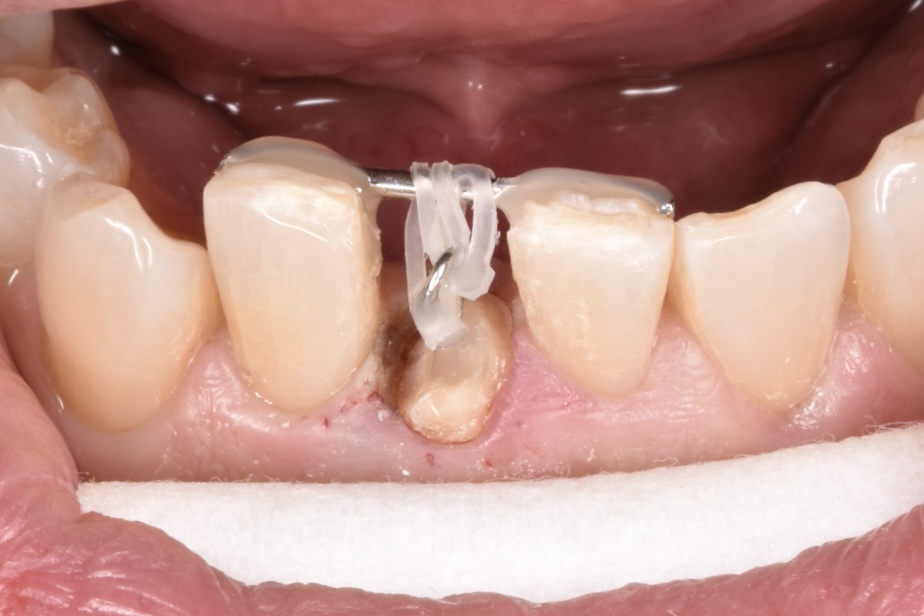

意図的挺出その後セラミック治療

歯が折れてしまっている現状では、このままセラミックをやりかえても予後が悪く長持ちしない点をお伝えしました。そこでご自身の歯を上に引っ張り出して骨からの距離を出してからセラミックで修復する意図的挺出(いとてきていしゅつ)をご提案させて頂きました。